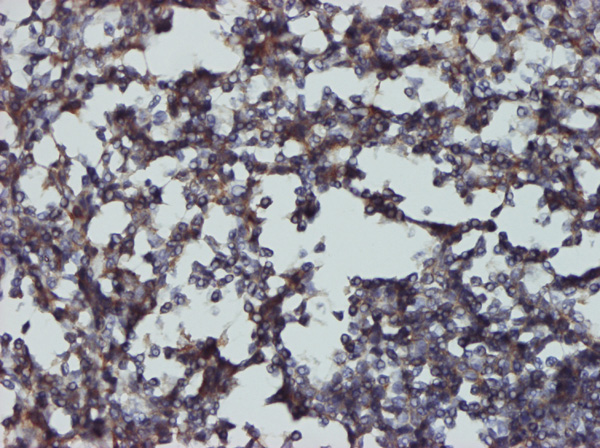

Immunoperoxidase of monoclonal antibody to CD48 on formalin-fixed paraffin-embedded human tonsil tissue.[antibody concentration 2 ug/ml]